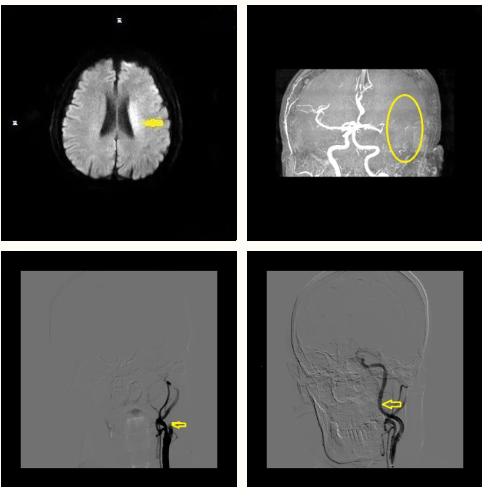

事情要从两年前说起。2021年8月1日,王大爷因为急性脑栓塞、左侧颈内动脉闭塞收入神经外科一病房治疗。由于情况紧急,赵德强主任团队立即为其进行了取栓手术。

手术非常成功,王大爷恢复良好,顺利回归正常生活。2023年2月1日,王大爷因房颤导致栓子脱落造成脑栓塞再次入院治疗,据家属描述老人未遵医嘱自行停服抗凝药物已达半年。由于栓塞面积大,而且位置靠近重要功能区,这给手术带来了极大的风险和难度。

情况危急,赵主任与团队反复研究并征得家属同意后,立即进行手术治疗。当日13:00王大爷在全麻下行急诊支架取栓手术,13:54取栓手术成功。术中取出大量栓子, 基底动脉恢复畅通。